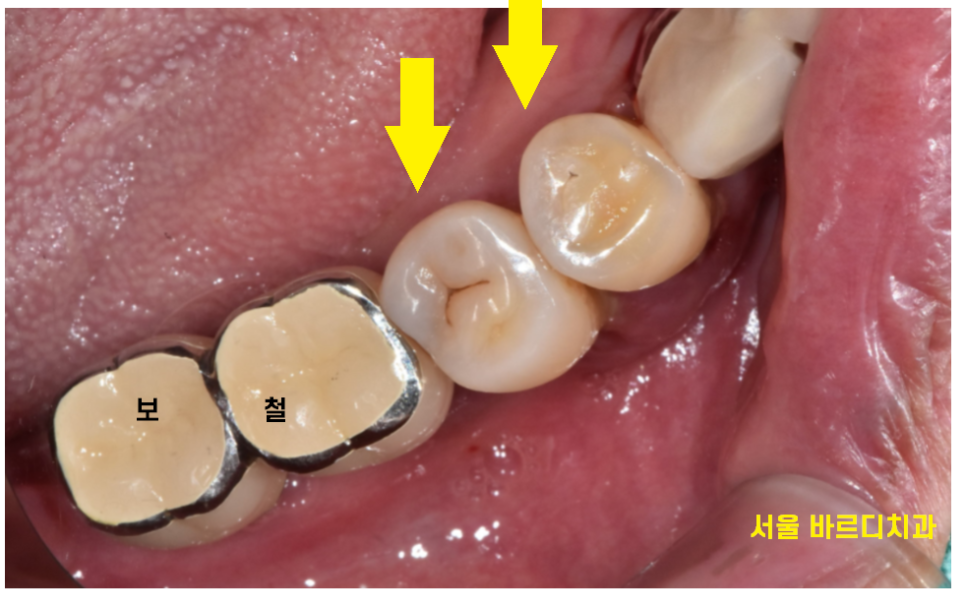

문제는..

뼈!!가 문제였습니다.

자연치 2개가 잇몸이 붓고

자꾸 피가나서 불편을 호소하셨거든요

뼈가 내려가긴 하였지만

그리고 발치 후 당일 뼈이식을 진행 후

뼈가 1차적으로 차면

그때 임플란트 수술을 진행하기로 하였습니다.